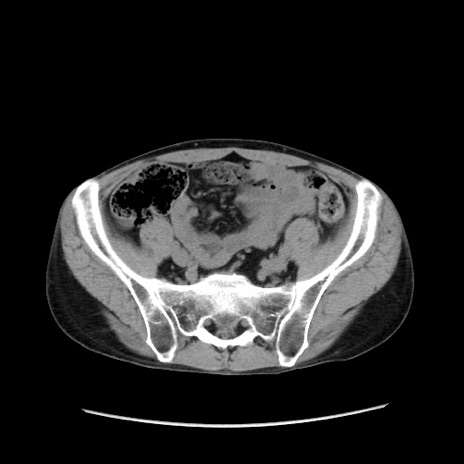

症例37(横断像)

【症例】40歳代 男性

【主訴】腹痛

【現病歴】4時間ほど前に電車に乗車中に臍部上より腹痛出現。徐々に増悪し起立困難となり、救急外来受診。生ものは数日食べていない。今朝お雑煮を食べた。

【身体所見】BT 36.8℃、BP 117/84mmHg、HR 91/min、SpO2 97%、苦悶様、腹部:臍上部広範囲圧痛あり、反跳痛±

【データ】WBC 8100、CRP 0.03